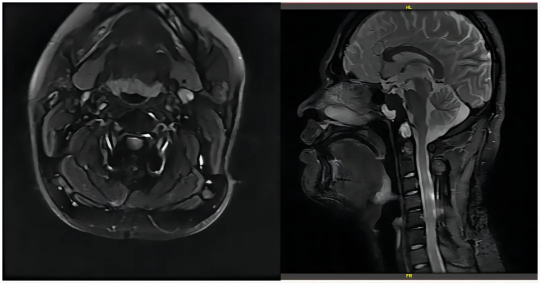

2020.4 术后治疗前(上图)